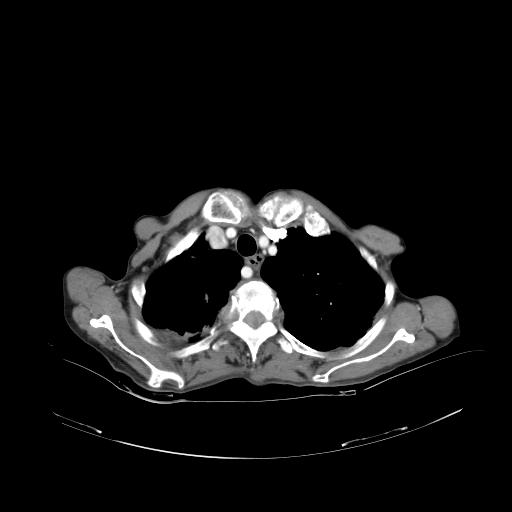

女,72岁,咳嗽一周余,突发右下肢无力二天。

pe:bp-140、80mmhg,精神可,伸舌居中,右上肢肌力正常,右下肢肌力0级,巴氏征+

来院做头颅+胸部ct平扫

遂加作增强:

胸部病变平扫35hu,增强强化至70hu

这个病人首先是胸部病变的定位到底是肺内还是肺外。仔细观察块影位于胸膜下,与胸膜间有透亮带,且近端血管未见明显推移而是引流样改变,形态分叶,说明这个病灶位于肺内胸膜下。很可能是腺癌,腺癌最易致颅内高密度转移灶。局部胸膜有侵犯。

本例颅内见多发大小不等高密度灶,有强化及水肿;另外,胸锁关节层面可能是第四胸椎及右侧肋骨起始部骨质欠连续,椎旁软组织肿胀,建议调骨窗观察。

诊断:右下肺癌伴颅内、胸椎、肋骨转移可能性最大。